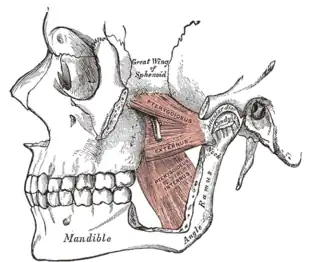

Muscles of mastication

The muscles of mastication are paired on each side and work together to produce the movements of the mandible. The main muscles involved are the masseter, temporalis and medial and lateral pterygoid muscles.

Left medial and lateral pterygoid muscles

Left medial and lateral pterygoid muscles Left temporalis muscle

Left temporalis muscle.png.webp) Left masseter muscle (red highlight)

Left masseter muscle (red highlight)

They can be thought of in terms of the directions they move the mandible, with most being involved in more than one type of movement due to the variation in the orientation of muscle fibers within some of these muscles.

- Protrusion – Lateral and medial pterygoid.

- Retraction – Posterior fibers of temporalis (and the digastric and geniohyoid muscles to a lesser extent).

- Elevation – Anterior and middle fibers of temporalis, the superficial and deep fibers of masseter and the medial pterygoid.[42]

- Lateral movements – Medial and lateral pterygoid (the ipsilateral temporalis and the pterygoid muscles of the contralateral side pull the mandible to the ipsilateral side).[35]

Each lateral pterygoid muscle is composed of 2 heads, the upper or superior head and the lower or inferior head. The lower head originates from the lateral surface of the lateral pterygoid plate and inserts at a depression on the neck of mandibular condyle, just below the articular surface, termed the pterygoid fovea. The upper head originates from the infratemporal surface and the infratemporal crest of the greater wing of the sphenoid bone. The upper head also inserts at the fovea, but a part may be attached directly to the joint capsule and to the anterior and medial borders of the articular disc.[42] The 2 parts of lateral pterygoid have different actions. The lower head contracts during mouth opening, and the upper head contracts during mouth closing. The function of the lower head is to steady the articular disc as it moves back with the condyle into the articular fossa. It is relaxed during mouth closure.[26]